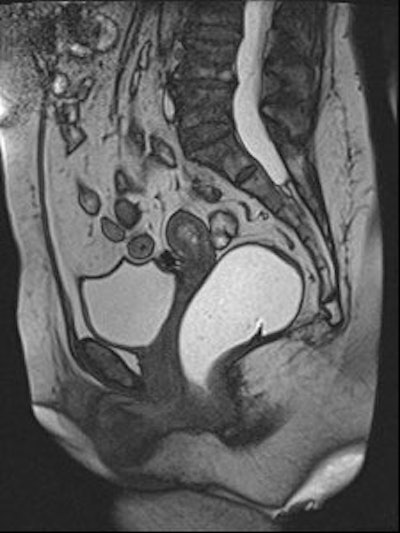

Sagittal late evacuation view shows a cystocele in the middle and posterior pelvic floor compartment. Image courtesy of Dr. Steve Halligan.